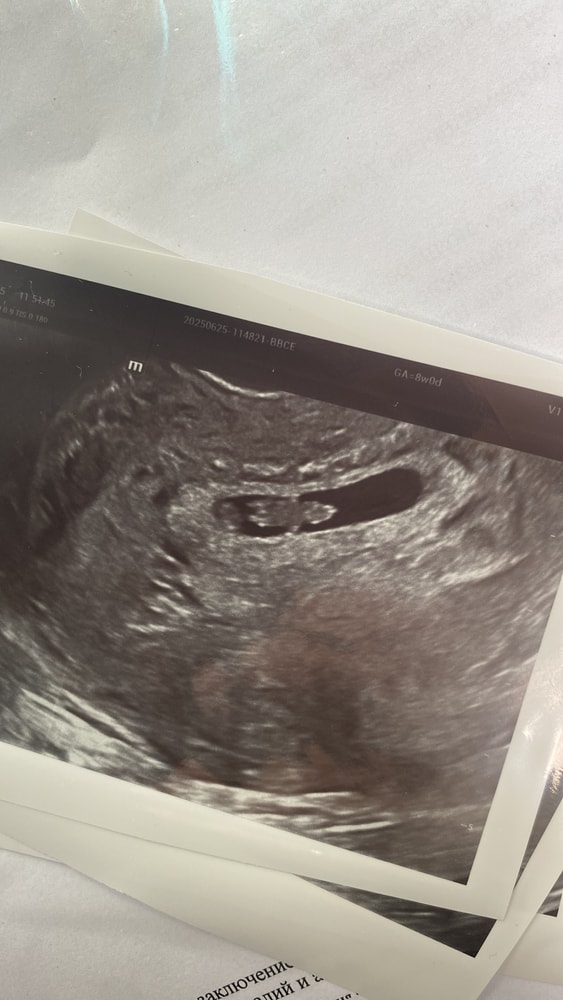

УЗИ 8 нед

Ну вот и первое узи состоялось))